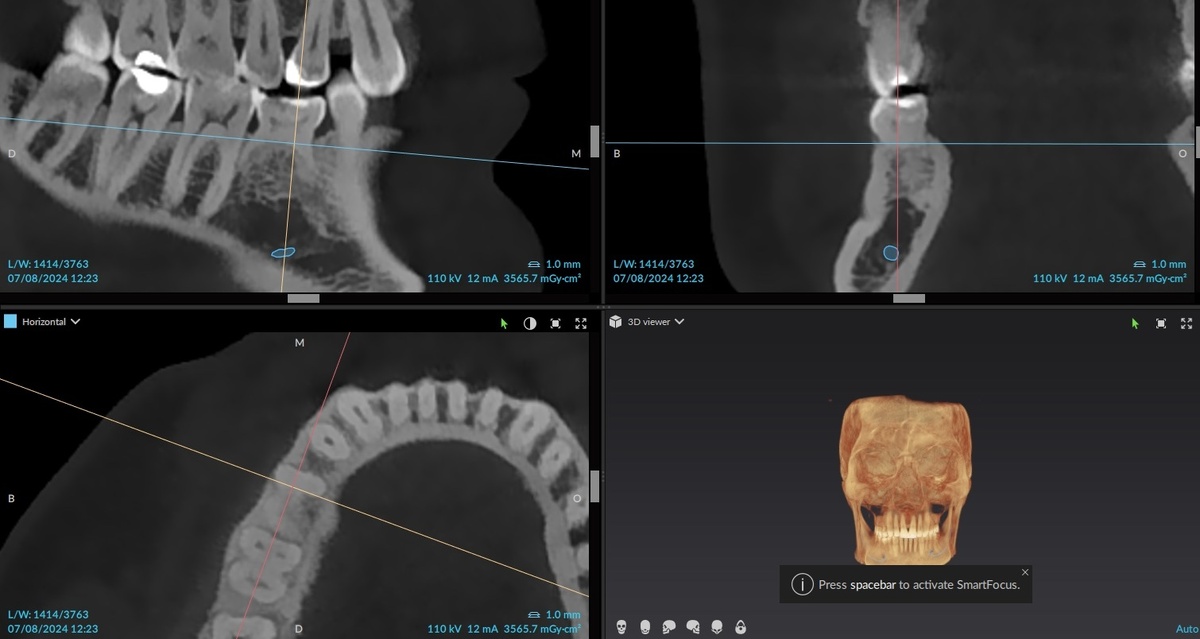

Срез КТ в области 8.5: